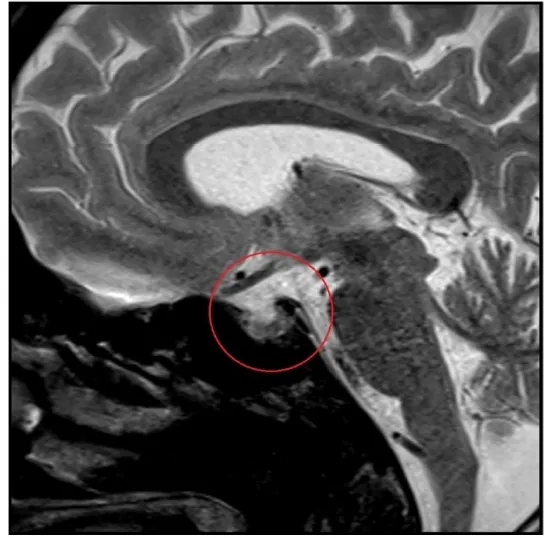

IRA + Icterícia: Um Caso que Exige Investigação Detalhada

IRA + Icterícia: Um Caso que Exige Investigação Detalhada